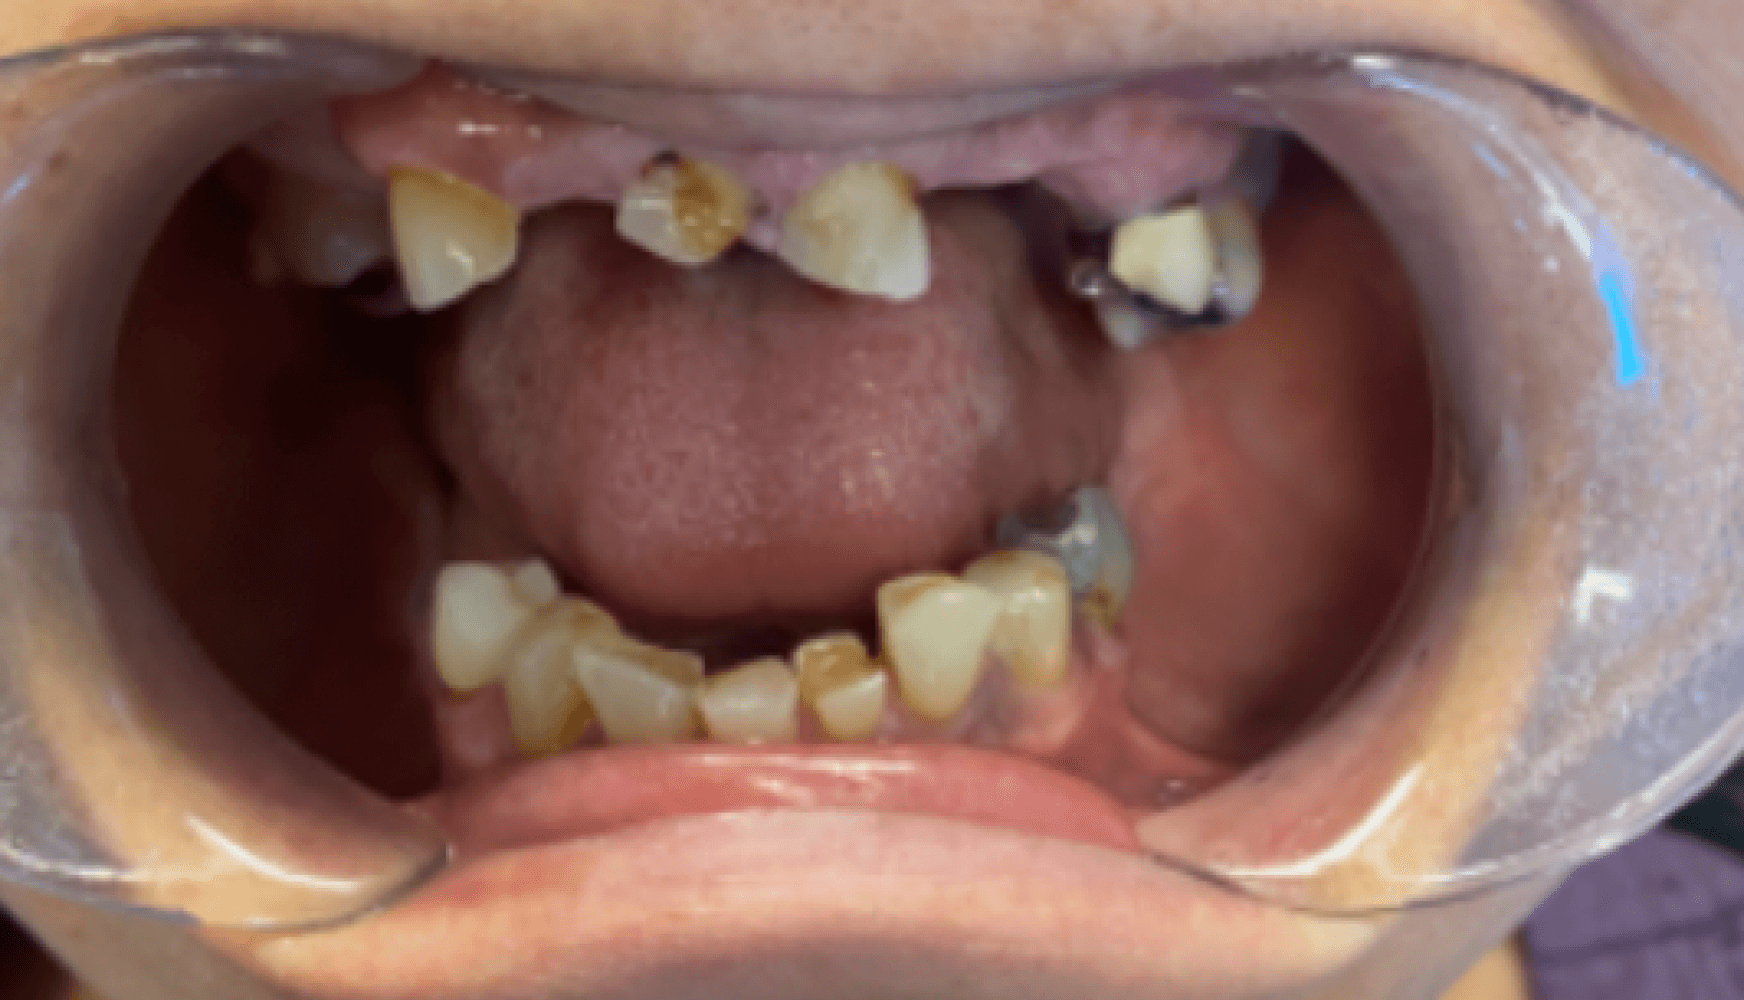

Fig. 1a, 1b, 1c, 1d: The patient’s dentition upon examination reveals significant reduction in VDO, a drastic left-to-right tilt in her smile line, and atrophy of the posterior mandibular ridge.

The patient presented with terminal dentition, multiple compromised and missing teeth, and a significant reduction in vertical dimension of occlusion (VDO) due to years of attrition and bruxism. The patient exhibited a drastic left-to-right tilt in her smile line, with significant atrophy of the posterior mandibular ridge. The right temporomandibular joint (TMJ) displayed a non-reducing disc and deviation to the right upon translation. These anatomical challenges, combined with the patient’s desire for improved function and aesthetics, necessitated a multi-phase treatment plan, beginning with immediate dentures and progressing to implant-supported dentures.

During the initial consultation, we reviewed the patient’s medical history and completed a thorough oral examination. The patient was found to have multiple broken and missing teeth, severe posterior ridge atrophy, and a collapsed bite due to years of tooth loss and bruxism. The patient’s VDO was significantly reduced, contributing to the functional challenges she experienced. We discussed the phases of her treatment plan, beginning with the fabrication of immediate dentures following extractions, and progressing to implant-supported dentures. Given the atrophy of the posterior mandibular ridge and the drastic smile line tilt, careful planning was required. The immediate dentures were scheduled for fabrication following her upcoming extraction and implant surgery.